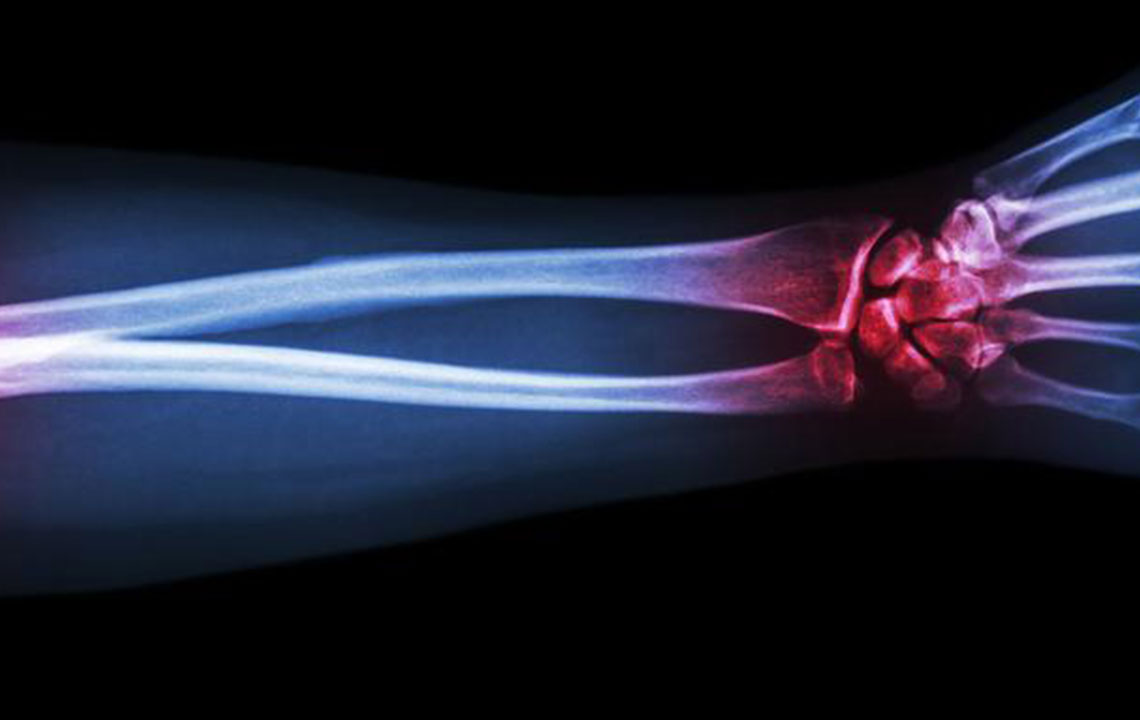

Gout is a type of arthritis that primarily attacks the joints and other body parts like the ears, wrists, knuckles, knee, ankles, and other small joints. It is often characterized by painful swelling, stiffness, and inflammation of these affected joints. The swelling and stiffness are mainly the results of excess levels of uric acid forming crystals in the joints. The pain is due to the inflammatory response to the crystals formed.

The most common sign of a gout attack is the night-time swelling of the big toe followed by redness, tenderness, redness, and gut-wrenching pain. This attack might continue for days or even weeks before the pain goes away completely. Swelling causes pain and pain induces swelling. Hence, it is important to address both.